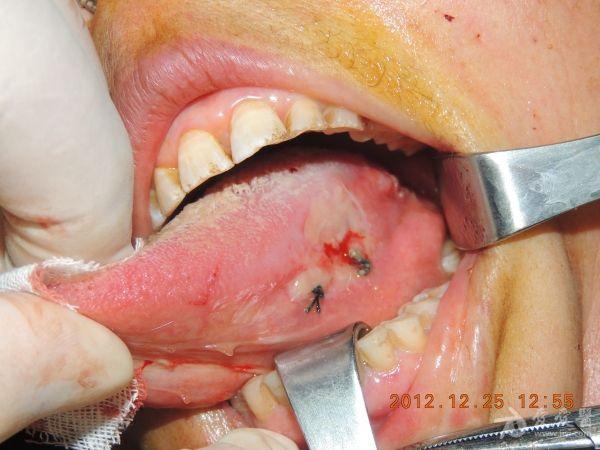

舌癌扩大切除+前臂皮瓣修复(游离皮瓣修复)

安徽医科大学第三附属医院口腔颌面外科病例

病例特点:1.患者,女,71岁

2.左侧舌部溃疡三年余

3.患者约三年前发现左舌缘有一约黄豆大小溃疡面,稍有疼痛,2010年10月在当地医院行病灶切除术,术后病理示:鳞状上皮增生伴低级别上皮内瘤变,术后三个月左右,原术区边缘又出现溃疡,曾全身用药(具体不详),效果不明显,溃疡逐渐增大,进食**性食物时疼痛,约八个月前病灶出现自发性疼痛,舌运动受限,至我院就诊,我科门诊拟左舌缘溃疡收入院,患者本次入院无异常感冒发热,饮食睡眠正常,两便畅。

手术名称:左舌颌颈联合根治+左前臂游离皮瓣移植修复术(备气管切开术)